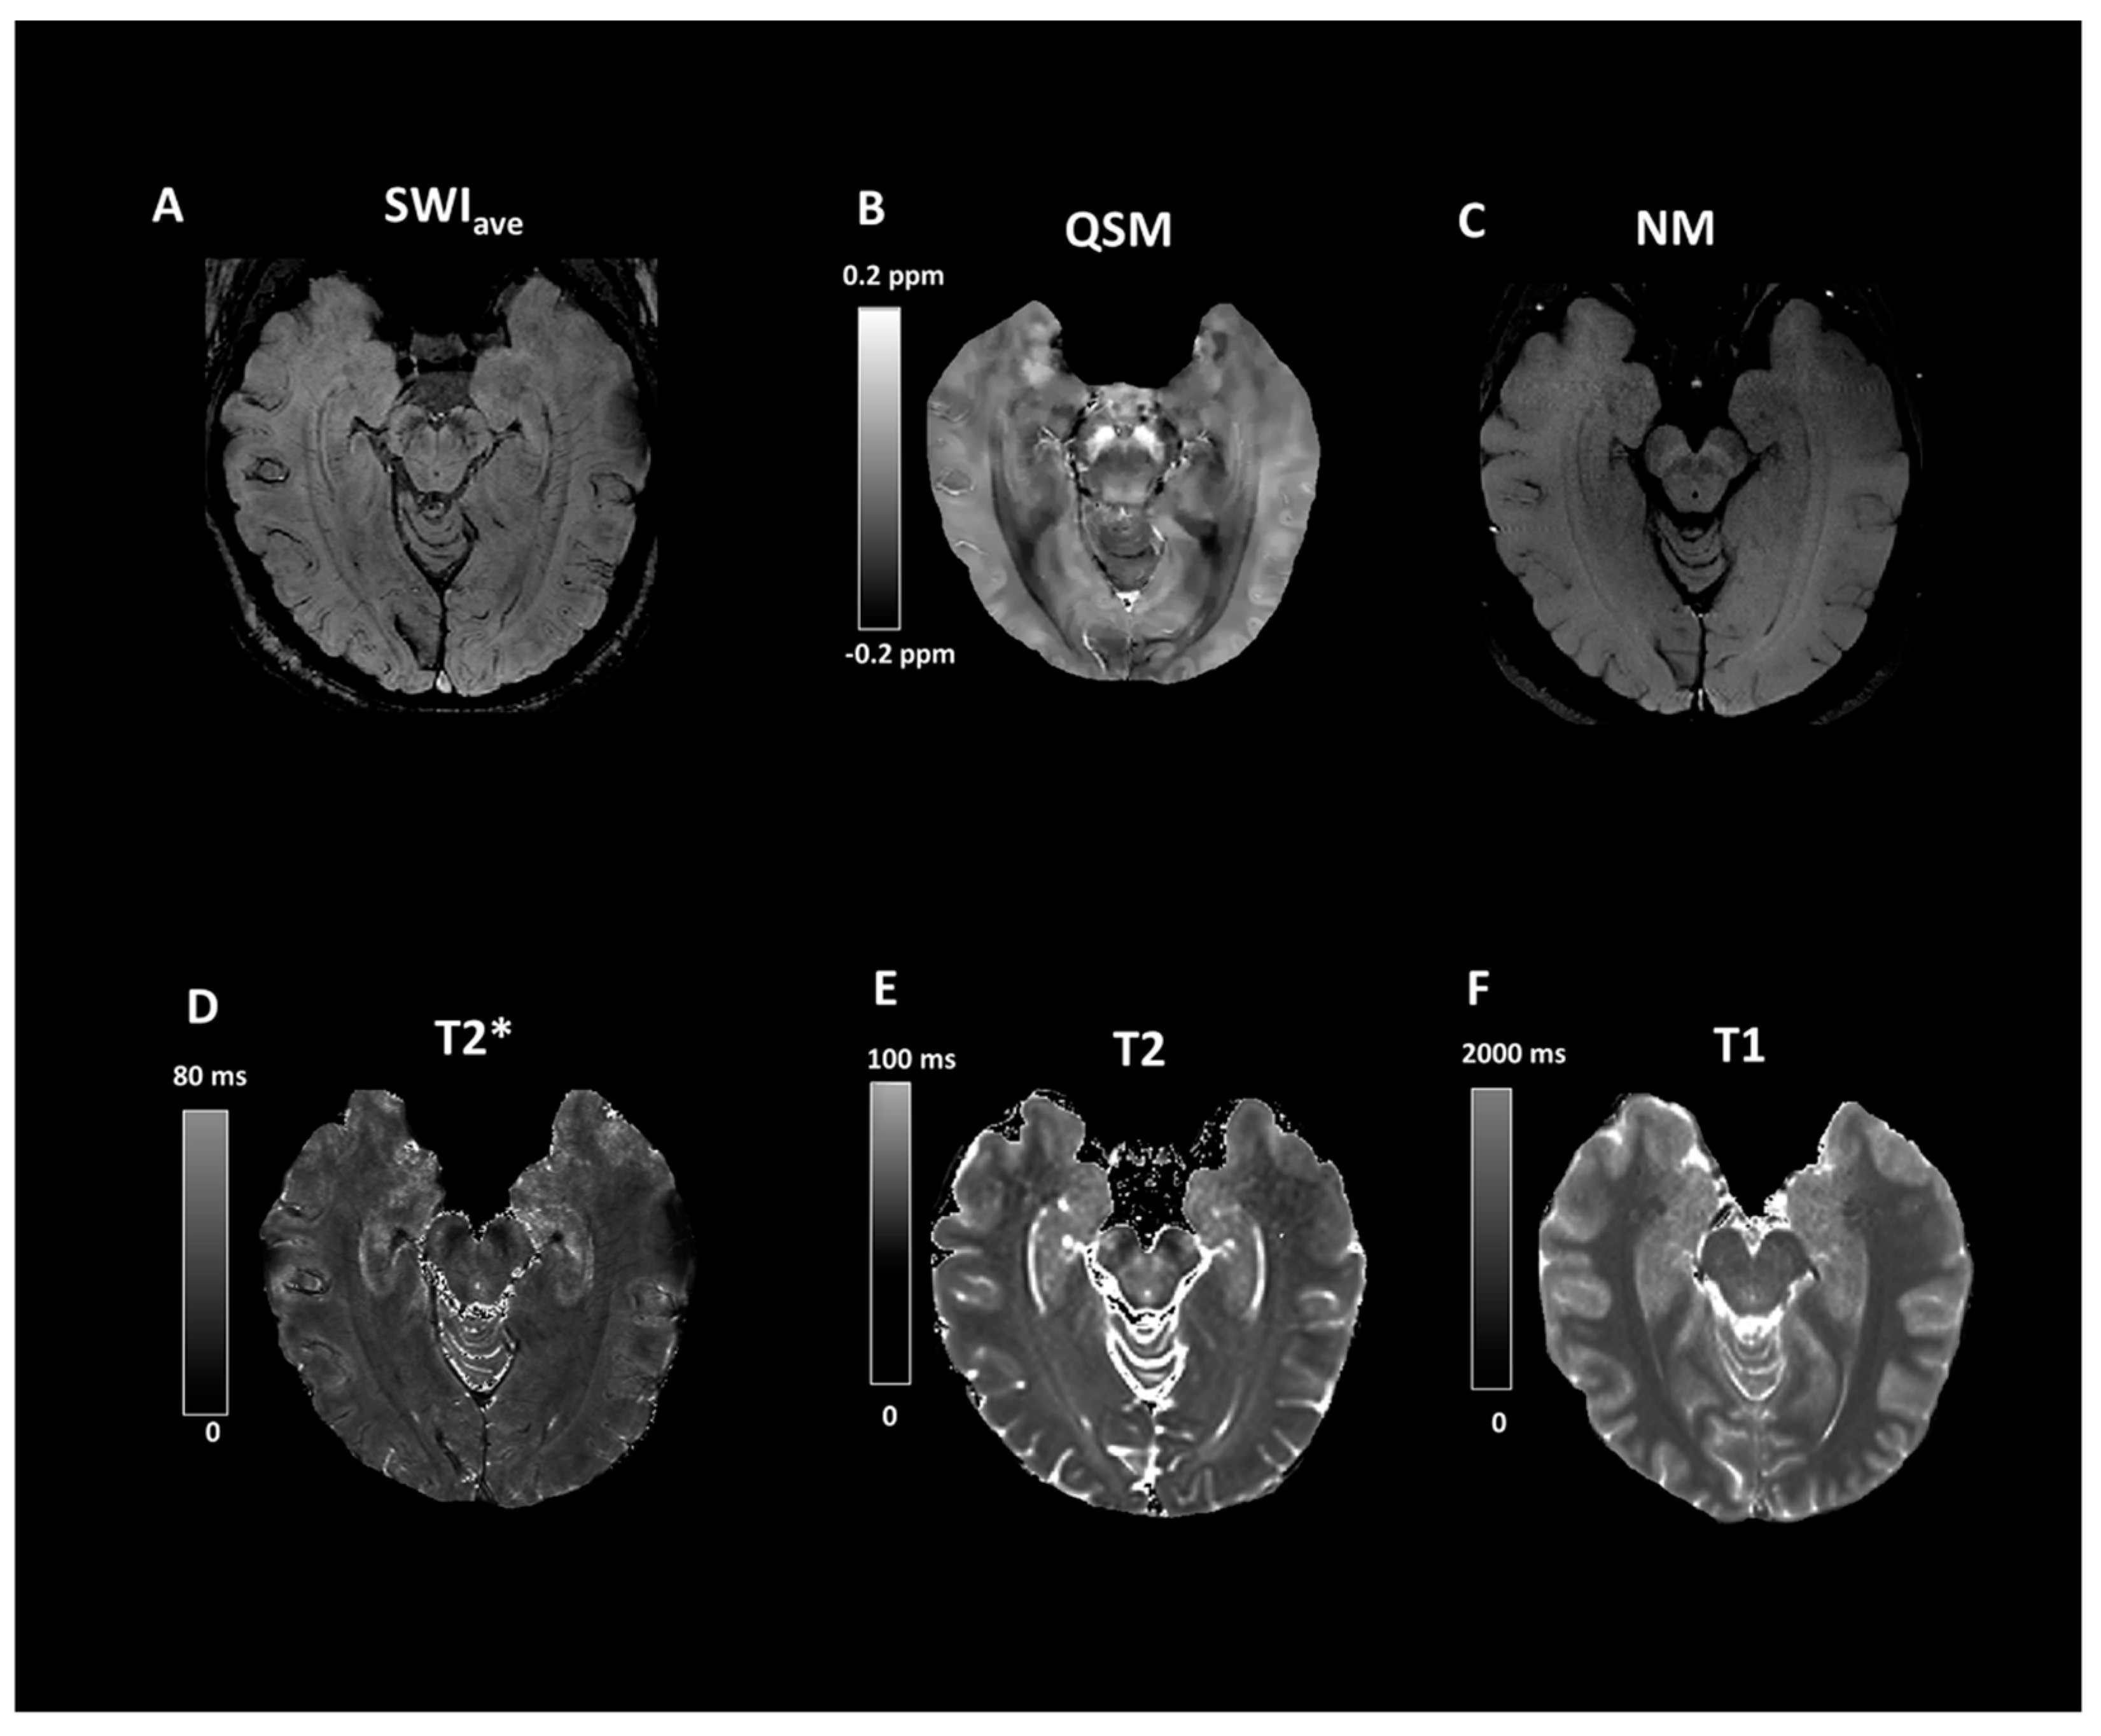

- Langley, J.; Huddleston, D.E.; Chen, X.; Sedlacik, J.; Zachariah, N.; Hu, X. A multicontrast approach for comprehensive imaging of substantia nigra. NeuroImage 2015, 112, 7–13. [Google Scholar] [CrossRef]

- Takahashi, H.; Watanabe, Y.; Tanaka, H.; Mihara, M.; Mochizuki, H.; Yamamoto, K.; Liu, T.; Wang, Y.; Tomiyama, N. Comprehensive MRI quantification of the substantia nigra pars compacta in Parkinson’s disease. Eur. J. Radiol. 2018, 109, 48–56. [Google Scholar] [CrossRef]